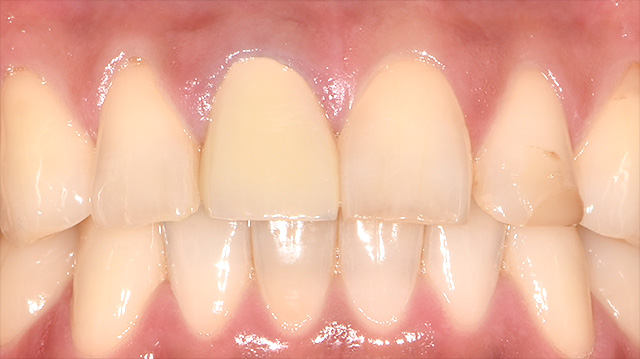

| 年代・性別 | 40代 男性 |

|---|---|

| 主訴 | 前歯の色が気になる |

| 治療回数 | 3回 |

| 治療期間 | 約1ヶ月 |

| 費用 | 仮歯 5,500円 ジルコニアクラウン 176,000円 |